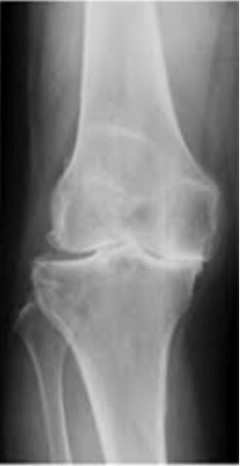

変形性膝関節症の進行度合い

変形性膝関節症の初期は50代からはじまり、歳を重ねていくごとに変形は進行していきます。

痛みを繰り返すから骨はどんどん変形していき、最終的には末期の変形になります。

病院でレントゲン・CT・MRIを撮って、『膝の変形がある。手術しか方法はない!』と医師から言われることがよくあります。